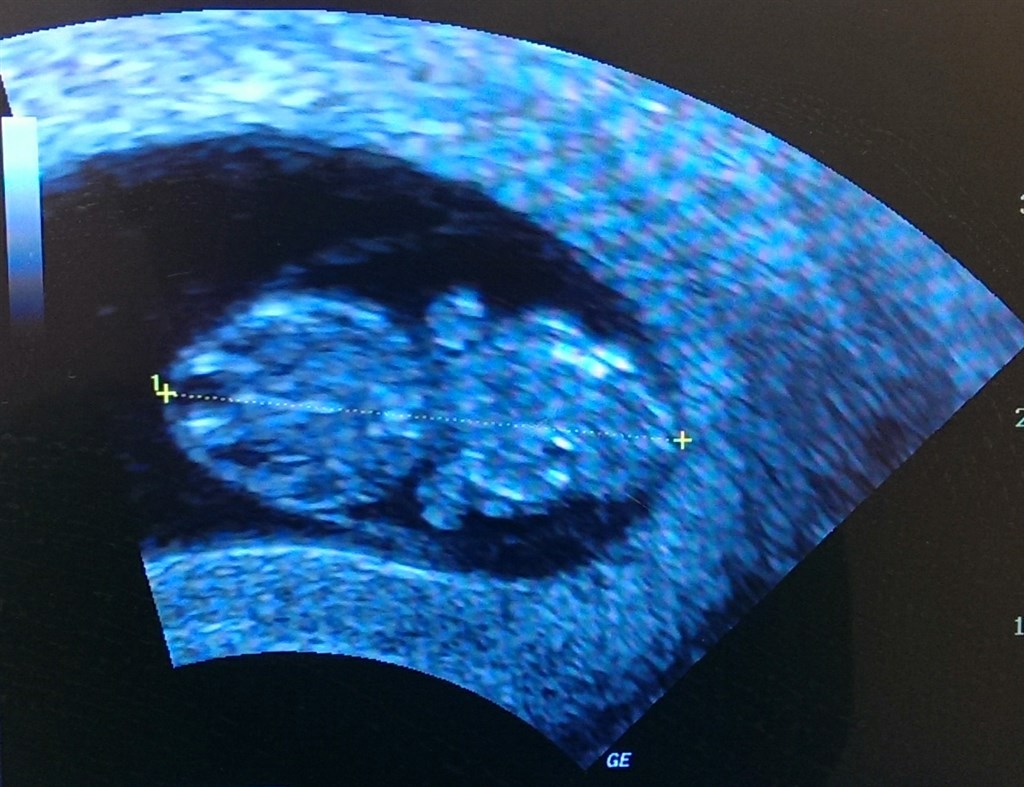

Var til scanning igen idag, nede på klinikken.. Iih sikke et dejligt syn! H*n ville ikke vende sig om, men med lidt bevægelse af mig, vendte h*n sig om

.. H*n lå i buddah stilling, havde rigtig fin hjertelyd, og vinkede lige så fint til mig

Jeg ville ikke andet, end bare at vise den bette frem